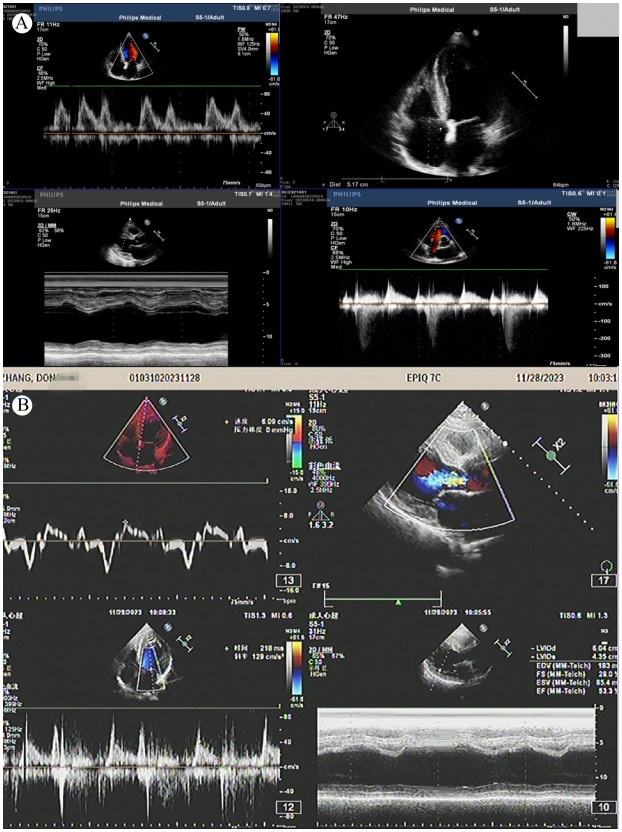

术后次日,患者神志转清,生命体征平稳,左侧肌力恢复至4级,复查头颅CT:右侧额叶小片状梗死(图 5)。予拔除气管插管、脱机,观察1 d后转心内科病房。复查肌钙蛋白Ⅰ: 13 ng/mL,超声心动图示(图 6A):左室增大伴左室多壁段收缩活动异常,左室射血分数45%。患者恢复迅速,出院时神志清楚,口齿清晰,左上肢肌力5-级,左下肢肌力5级,住院共11 d。出院诊断:(1)急性下壁、右室心肌梗死、冠心病、心功能KillipI级;(2) CAAs;(3)急性额叶脑梗死;(4)高血压病。出院后给予氯吡格雷75 mg 1次/d、阿司匹林100 mg 1次/d、瑞舒伐他汀10 mg 1次/d,美托洛尔缓释片23.75 mg 1次/d,随访2个月,患者心功能正常(门诊复查心超见图 6B),四肢肌力正常,言语清晰,未遗留明显后遗症。

| 注:A为术后第6天心功能下降;B为出院2个月后心功能好转 图 6 患者的超声心动图 |